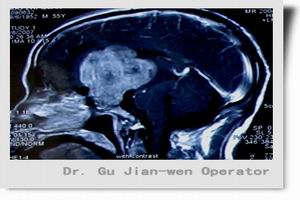

1.以往採用的氣腦造影術因併發症多、敏感性低而被淘汰,現多根據臨床表現選擇CT或MRI檢查。CT是松果體腫瘤的首選檢查,可做增強及冠狀面掃描。CT引導活檢可於病灶局部獲取組織,明確病理診斷。Fedorcsak等在1989~1996年期間進行523次CT引導定向活檢術,認為本法完全有效,對顱內腫瘤的組織學診斷、制定合適的治療方案很有必要。

2.MRI對松果體母細胞瘤診斷有獨到優點,松果體母細胞瘤起源於松果體腺,惡性程度大,具浸潤性,生長快,易轉移,病人存活期短,因而早期診斷治療十分重要。MRI顯示松果體腫瘤區域的高信號以及清晰可見腫瘤侵入第三腦室的程度。